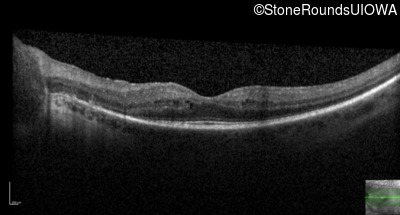

20/40 -1

OCT Stack

20/32 -1